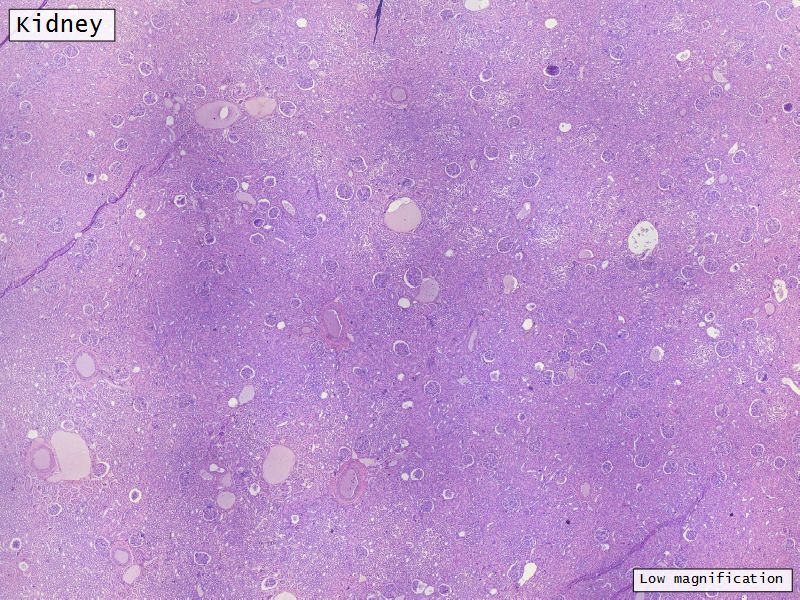

Capsule

Cortex

Medulla

Multilobar

Appearance

Renal corpuscles

Convoluted tubules

Loops of Henle

Collecting tubules